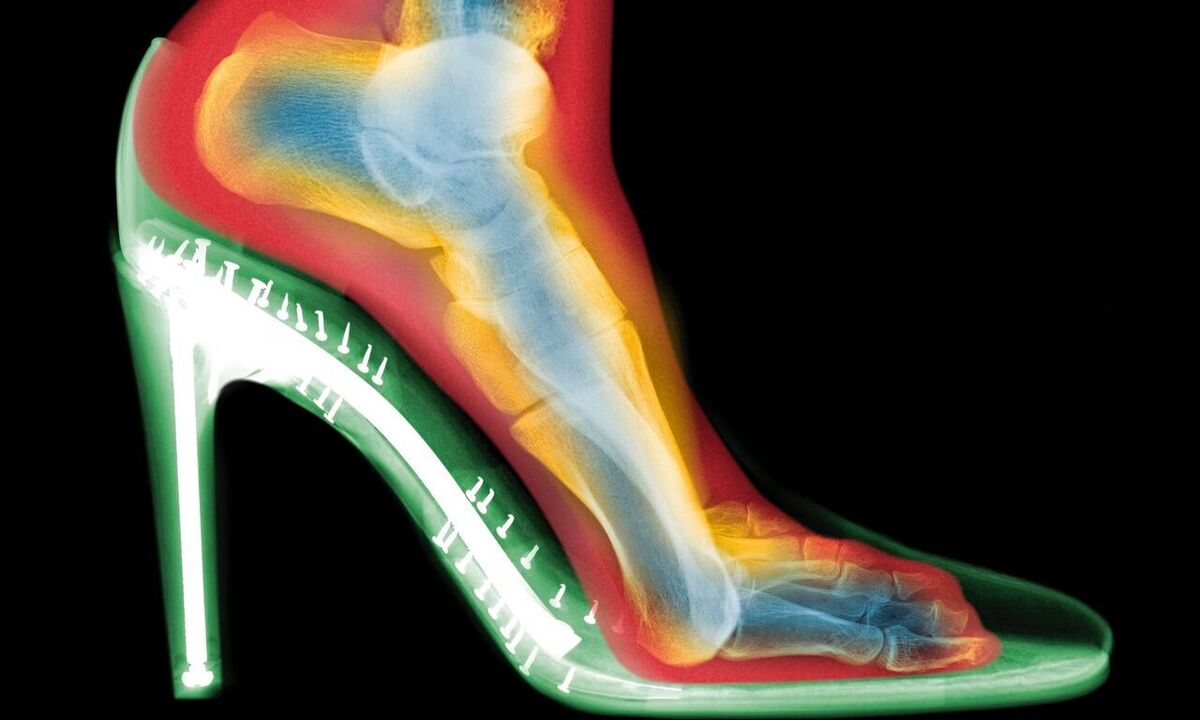

گلدبرگ دو اسکن از پای یک فرد تهیه کرد: یکی بدون کفش و دیگری با کفش پاشنهبلند. تفاوتها چشمگیر بود:

فشردگی انگشتان: انگشتان پا در کفش به هم فشرده شده بودند.

انحراف شست پا (بونیون): مفصل انگشت شست به طرف بیرون متمایل شده بود.

انگشتان چنگالی: انگشتان کوچکتر برای حفظ تعادل، حالتی قفلشده و خمیده به خود گرفته بودند.